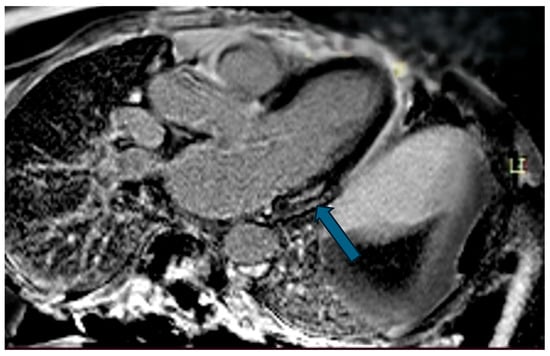

| Case | Patient (Sex, Age) | Symptoms | MAD (mm) | Valvular Issues | LGE | Other Details |

|---|---|---|---|---|---|---|

| 1 | Female, 61 years old | Syncope | 11 | MVP, mitral regurgitation | Lateral | Holter: atrial tachycardia and ventricular ectopy; cardiology follow-up planned for possible mitral valve repair |

| 2 | Male, 52 years old | Syncope and atypical chest pain | 10 | - | Lateral | History of ventricular arrhythmias; cardiology follow-up and Holter monitoring recommended |

| 7 | Female, 53 years old | Extrasystole and syncope | 15 | MVP, valvular regurgitation | Basal-lateral | Extensive MAD with MVP and LGE; increased arrhythmic risk; antiarrhythmic therapy considered. |

| 8 | Female, 63 years old | Aortic and mitral regurgitation | 11 | Aortic and mitral regurgitation | Lateral | Aorto-mitral regurgitation with septal hypokinesia; mitral valve repair performed; heart failure therapy started. |

| 9 | Male, 45 years old | Palpitations and vertigo | 10 | - | Lateral | Basal lateral LGE; regular clinical and ECG follow-up recommended |